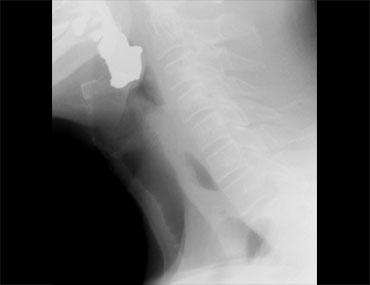

Các hình ảnh là của một bệnh nhân có cảm giác vướng họng (globus sensation).

Nguyên nhân là do trào ngược nặng và tình trạng tăng trương lực cơ nhẫn hầu thứ phát.

Thoát vị cạnh thực quản lớn kèm trào ngược là nguyên nhân gây ra các triệu chứng.

Thăm khám thực quản

Luôn theo dõi quá trình di chuyển của barium qua thực quản cho đến khi vào dạ dày.

Các rối loạn tại vùng nối thực quản-dạ dày thường được bệnh nhân cảm nhận như một vấn đề ở vùng họng.

Lý giải cho điều này là ở những bệnh nhân có tắc nghẽn đoạn xa, trào ngược dạ dày-thực quản hoặc rối loạn vận động, cơ nhẫn hầu phải hoạt động rất mạnh để ngăn thức ăn trào ngược lại vào hầu họng — kèm theo nguy cơ hít sặc.

Trương lực cơ tăng cao này tạo cho bệnh nhân cảm giác có vật gì đó trong cổ họng.